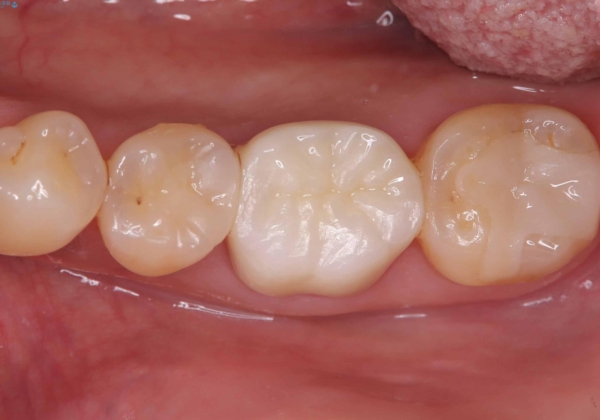

- 銀歯2本の下が虫歯になっていたので、フルジルコニアクラウンとセラミックインレーで治療を行いました。

適合が良い被せ物を入れるために、歯の境としっかり合わせた仮歯を入れ、歯茎の状態を良くしてからシリコンで型取りをしています。